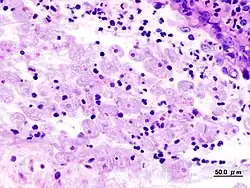

W celu diagnostyki laboratoryjnej zakażenia pełzakiem czerwonki wykonuje się preparaty (bezpośrednie oraz barwione) kału, w których metodą mikroskopową poszukuje się cyst Entamoeba histolytica.

Do potwierdzenia zakażenia pełzakiem czerwonki konieczne jest również badanie materiału genetycznego pierwotniaka; wykazano bowiem, iż istnieją inne gatunki pełzaków: Entamoeba dispar i Entamoeba moschkovskii, które są morfologicznie i mikroskopowo identyczne z E. histolytica, lecz nie są patogenne i zakażenie nimi nie wymaga leczenia.